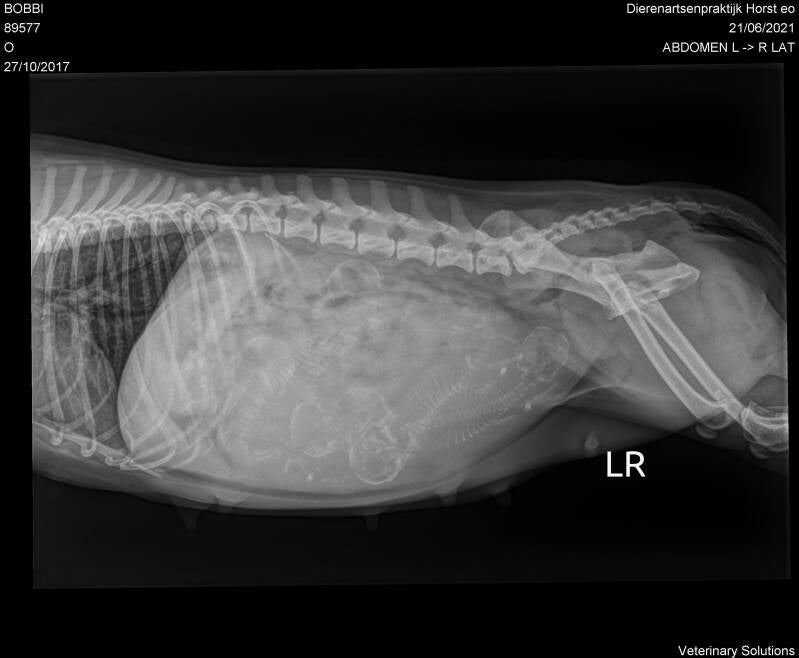

In de ochtend heb ik een röntgenfoto van Bobbie laten maken en toen kreeg ik het heugelijke nieuws dat Bob zwanger is van 5 pups! Mijn poule uitslag klopte dus niet, want ik dacht dat er 4 pups in haar buikje zouden zitten.

Op de foto hieronder kun je de kleintjes zien!